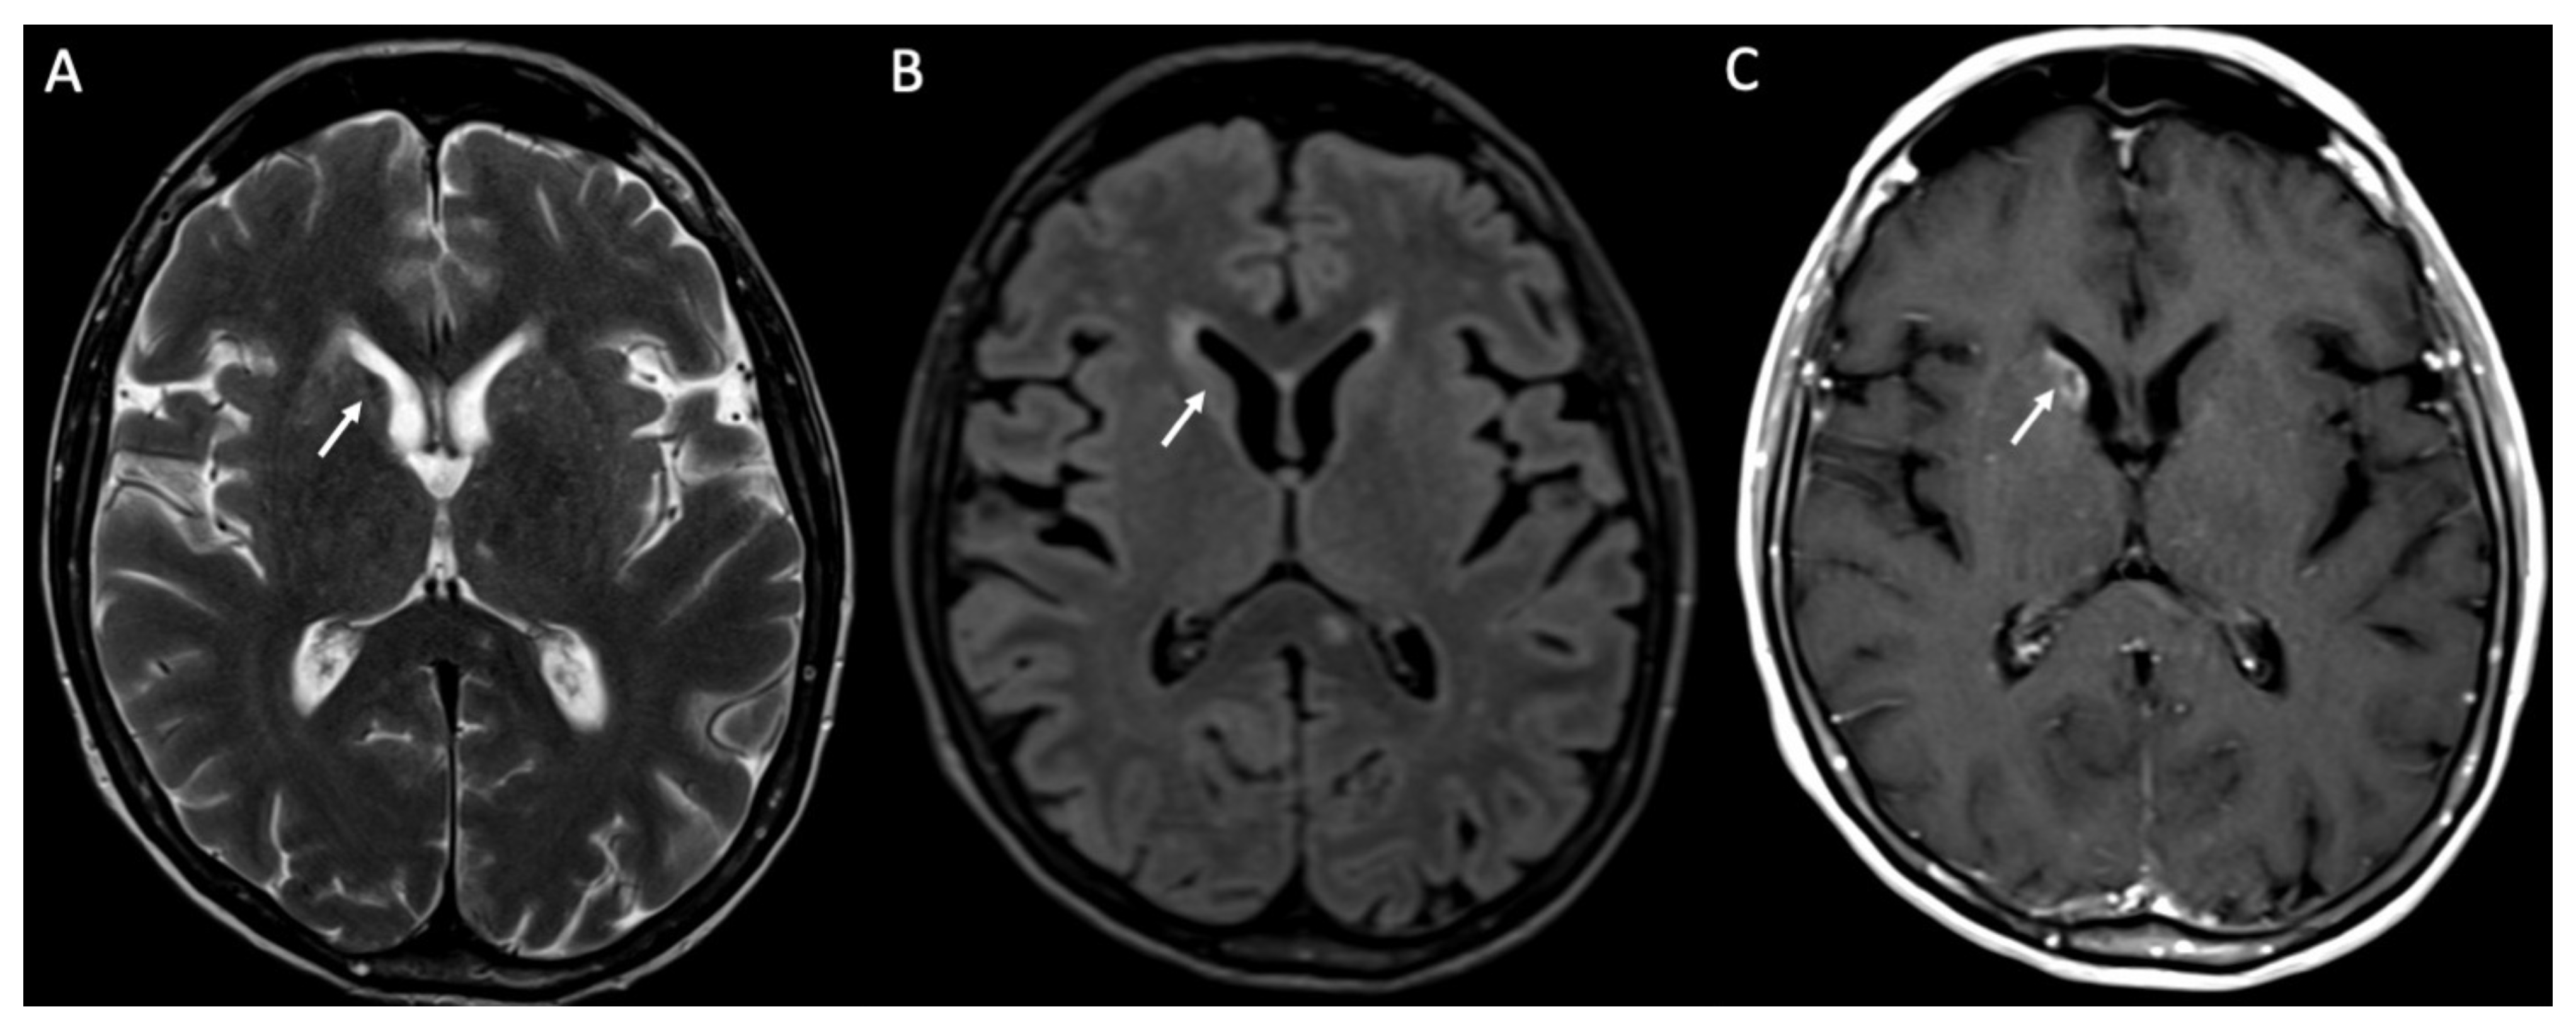

Complications are quite common [19]. The most common one is hydrocephalus, which is usually mild and transient (Figure 5) [20]. It can be caused by either blockage of CSF resorption due to inflammatory debris or aqueductal obstruction [7]. It can be easily detected by both CT and MRI [1]. Rarely, ventricular dilatation may be permanent, a condition called “arrested hydrocephalus”, which does not require treatment [1,21].

Figure 5.

Axial DWI (A), ADC (B), T2 (C), FLAIR (D), and enhanced T1 (E) show purulent material in the lateral ventricles bilaterally (arrowheads in A–E), with restricted diffusion, in a patient with Streptococcus Pneumoniae meningitis. Note also the recent ischemic lesions in the left nucleo-capsular region, which show faint contrast enhancement after contrast injection (arrows in A–E). There is also enlargement of the lateral ventricles due to hydrocephalus.

Subdural effusion is present in almost 33% of patients with meningitis, and it is more frequent in pneumococcal infection (Figure 6) [19]. It is related to irritation of the dura mater or inflammation of subdural veins [22]. They are usually located at the frontal and temporal convexities and resolve spontaneously [1]. On MRI, they appear as crescentic subdural fluid collections isointense to CSF [23].

Ventriculitis is often associated with meningitis, probably because of the backflow of purulent material in the CSF from the extraventricular spaces to the ventricles. On MR, it appears as areas of restricted diffusion within the ventricular system, which show hyperintensity on T2, FLAIR, and T1 without contrast enhancement (Figure 3 and Figure 5) [32]. Concomitant linear subependymal enhancement of the ventricular system adjacent to the purulent material can also be present (Figure 8).

Figure 8.

Axial DWI (A), ADC (B), T2 (C), FLAIR (D), and enhanced T1 (E) show purulent material in the lateral ventricles bilaterally (arrows in A–D) with linear subependymal enhancement (arrowheads in E) in a patient with Hemophilus influenzae meningitidis.